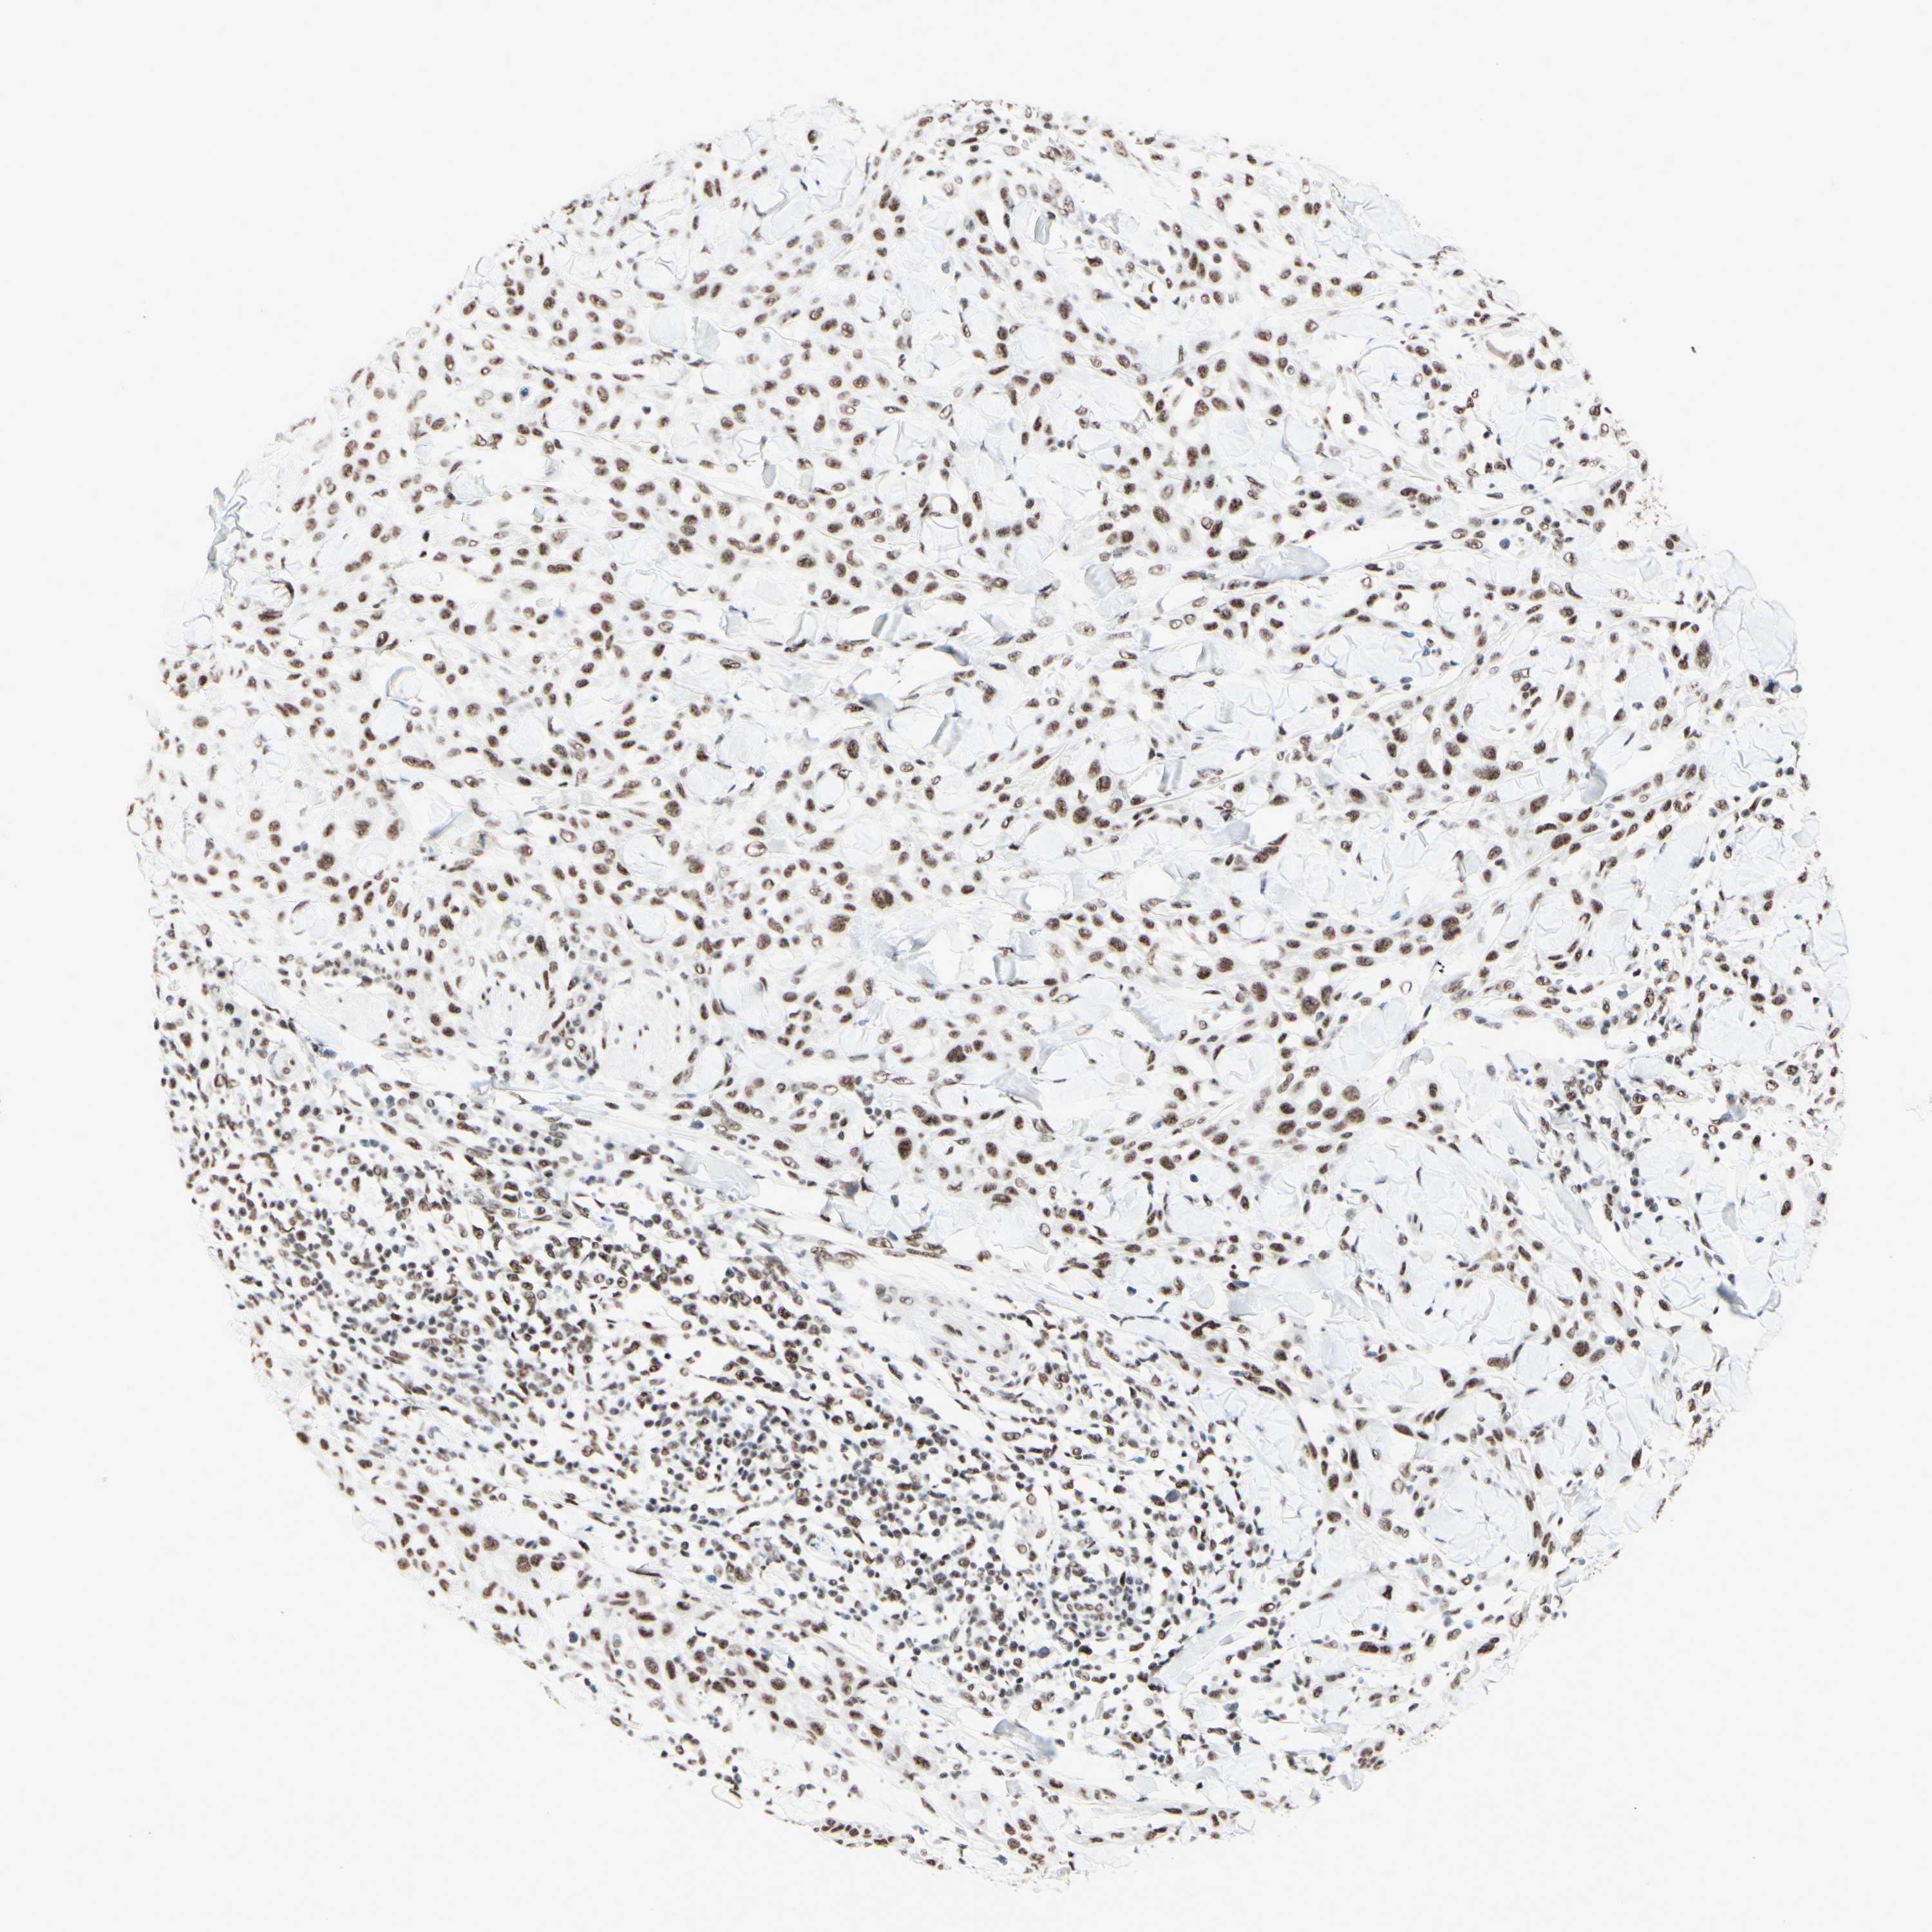

SKIN CANCER - Protein expressioni

A mouse-over function shows sample information and annotation data. Click on an image to view it in a full screen mode. Samples can be filtered based on level of antibody staining by selecting one or several of the following categories: high, medium, low and not detected. The assay and annotation is described here.

Antibody stainingi

Antibody staining in the annotated cell types in the current human tissue is reported as not detected, low, medium, or high, based on conventional immunohistochemistry profiling in selected tissues. This score is based on the combination of the staining intensity and fraction of stained cells.

Each image is clickable and will lead to virtual microscopy that enables deeper exploration of all samples and also displays staining intensity scores, fraction scores and subcellular localization as well as patient and tissue information for each sample.

Antibody HPA010550

Staining

High

Medium

Low

Not detected

Intensity

Strong

Moderate

Weak

Negative

Quantity

>75%

75%-25%

<25%

None

Location

Nuclear

Cytoplasmic/membranous

Cytoplasmic/membranous,nuclear

Squamous cell carcinoma, NOS

Basal cell carcinoma